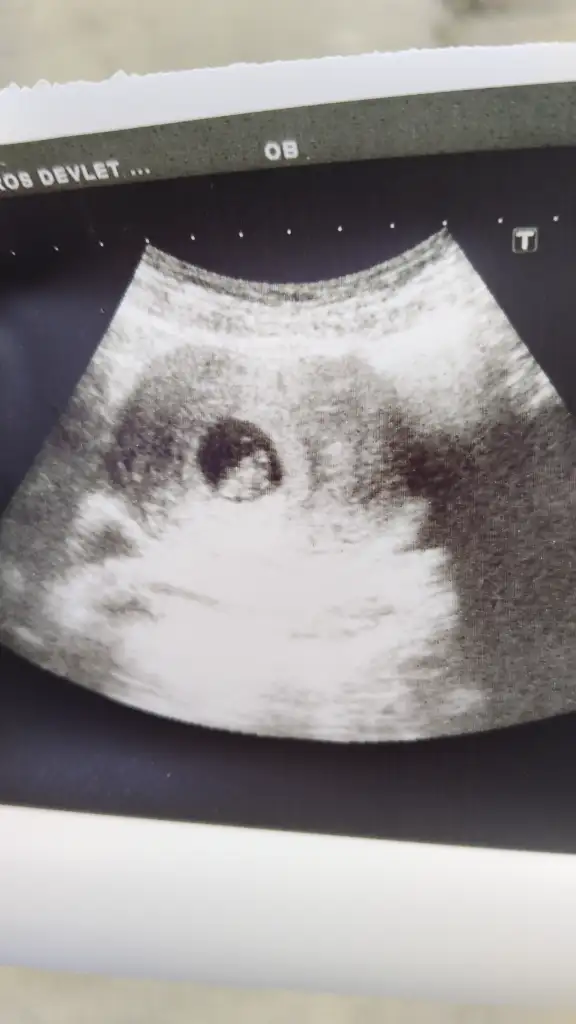

Merhaba hanımlar bugün 7 haftalık olduk ve kalp atışı için gittim çok şükür duyduk ve ayrıca artık ultrasyonda gorunuyo benim ufaklık ❤️